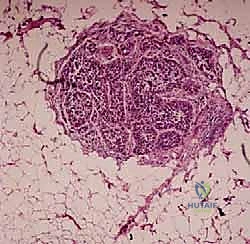

هنا تبرز أهمية الخزعة؛ فالتصوير الإشعاعي مهما كان متقدماً لا يمكنه تأكيد نوع الخلايا بنسبة 100%. التقييم النسيجي تحت المجهر هو الدليل القاطع الوحيد.

قراءة تقرير علم الأمراض (الباثولوجي): ماذا بعد الخزعة؟

تستغرق نتائج الخزعة عادة من أسبوع إلى أسبوعين. هذه الفترة قد تكون مليئة بالقلق للمريض وعائلته، ولكنها ضرورية لقيام طبيب علم الأمراض (Pathologist) بفحص الخلايا تحت المجهر وإجراء صبغات مناعية كيميائية (Immunohistochemistry) لتحديد النوع الدقيق للورم.

بمجرد صدور التقرير، يقوم الأستاذ الدكتور محمد هطيف بمناقشة النتائج بشفافية وأمانة طبية تامة مع المريض.

- إذا كان الورم حميداً: قد يكتفي بالمراقبة الدورية، أو يوصي باستئصال بسيط إذا كان الورم يسبب ألماً أو يهدد بكسر العظم.

- إذا كان الورم خبيثاً (ساركوما): يتم وضع خطة علاجية شاملة (Multidisciplinary approach) قد تتضمن العلاج الكيميائي، العلاج الإشعاعي، والجراحة الكبرى لاستئصال الورم مع الحفاظ على الطرف (Limb Salvage Surgery).